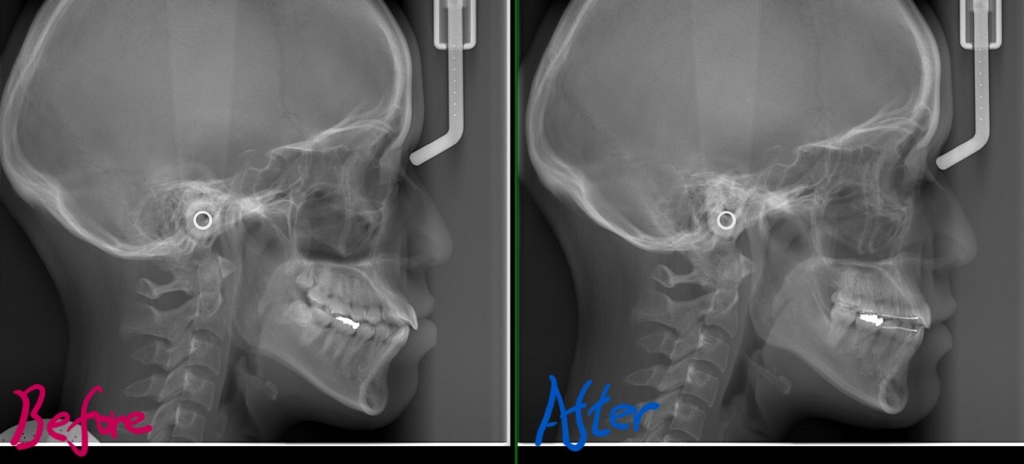

レントゲン写真でも比較してみましょう

左側が矯正治療前、右側が矯正治療後